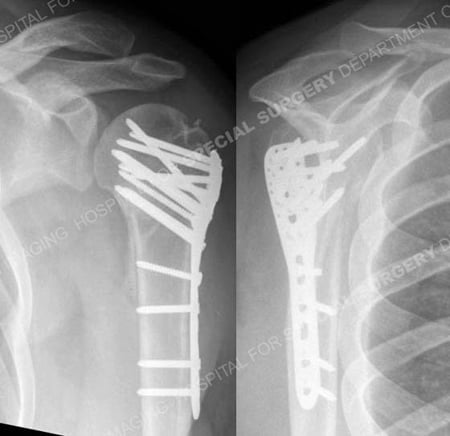

Radiographs of proximal humerus fracture and associated shoulder dislocation from a case example presented by the orthopedic trauma service at Hospital for Special Surgery.

Anteroposterior and lateral radiographs a comminuted 4-part proximal humerus fracture and associated shoulder dislocation with medial comminution.